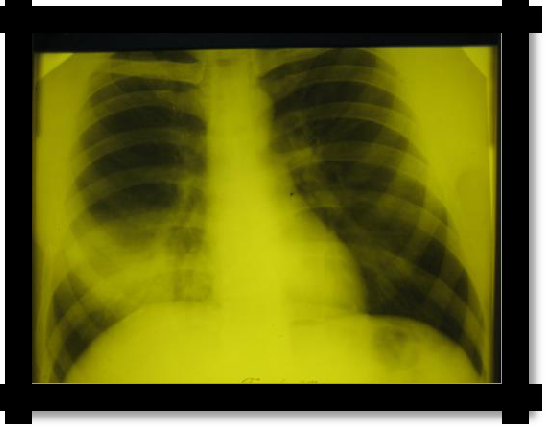

1. X-ray homogeneous dimming is determined in the lower part of the pulmonary field with a characteristic oblique upper border for exudate and a more horizontal upper border for transudate. In the latter case, the process is often two-way. There is a shift in the mediastinal organs to a healthy side.

Pic 2.4 The line of Damoiso-Ellis-Sokolov (1); The Garland Triangle (2)

and the Rauchfus-Grocco Triangle (3) with exudative pleurisy.

Pic 2.5 Left-

sided exudative pleuritis